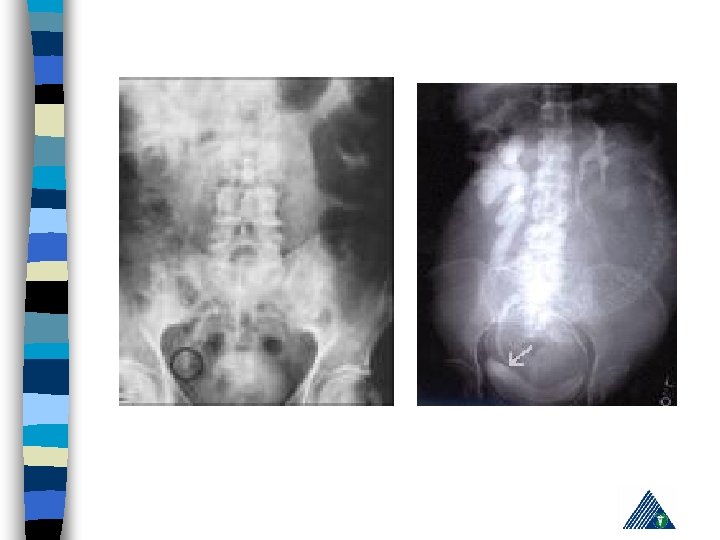

R: Appendicitis - Cholelithiasis n urinalysis: hematuria n KUB n IVP n Computerized Tomography n Pain management, hydration, hot bath n Treatment of the underlying cause n

Radiologic Imaging n n n KUB (loss of psoas or renal contour) IVU (delayed renal function, nonhomogenous collecting system) USG (lumbar hematoma and urinoma lokalizasyonu) Computerized Tomography Renal angiography